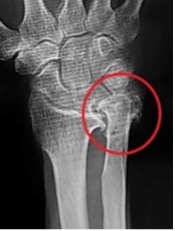

関節リウマチ患者に対する腱移行および手関節形成術

手関節の変形により腱断裂(特に伸筋腱)が生じ、急に指が伸びなくなる患者さんがいます。小指から始まり、比較的早期に手術をしない薬指中指と断裂が進行します。

断裂が進行しないように手関節の形成と、切れた腱に対しては直接縫合することは困難なため、隣接する正常な腱を用いて腱移行や腱移植を行ないます。

術前(レントゲン)

術後(レントゲン)